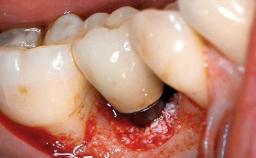

Removal of a Malpositioned Implant and Direct New Implant Placement with Simultaneous Contour Augmentation using GBR

A 35-year old female patient was referred to the Department of Oral Surgery and Stomatology at the University of Bern, Switzerland, for examination of an implant site that had exhibited clinical signs of slightly delayed wound healing. In addition, the referring clinician found no evidence for a facial bone wall when she raised a flap to gain access to the implant for abutment connection. Four months earlier, she had inserted a bone-level implant in a single-tooth gap, where the lateral incisor had been extracted due to a chronic periapical lesion on the mesial aspect of the root. Implant placement was combined with simultaneous bone augmentation using deproteinized bovine bone mineral (DBBM, Bio-Oss®; Geistlich, Wolhusen, Switzerland) and a collagen membrane (Bio- Gide®; Geistlich), followed by primary wound closure. The patient also provided the postsurgical radiograph that displayed the implant with a 3.5-mm healing cap.